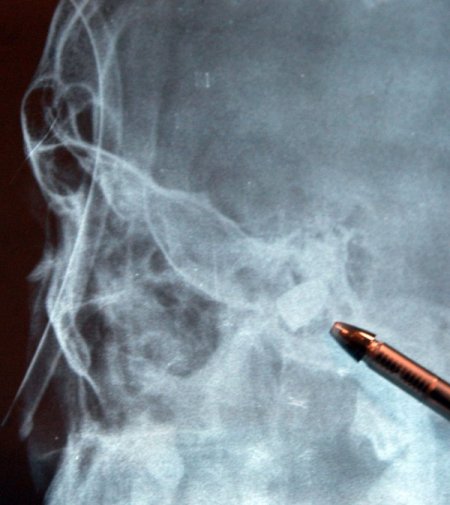

Mithatpaşa Mahallesi Karşıyaka Caddesi'nde meydana gelen olayda, kuzeni 18 yaşındaki Emre Köten ile birlikte bir yakınının düğününe gitmek için yola çıkan Mehmet Ali Şerbetçi, bir anda kanlar içerisinde kalarak yere yığıldı. Şerbetçi, çevredekiler tarafından çağrılan ambulansla Gaziantep Üniversitesi Tıp Fakültesi'ne götürüldü. Gencin burada çekilen röntgeninde kafatasında bir adet mermi çekirdeği belirlendi. Daha sonra Gaziantep Avukat Cengiz Gökçek Devlet Hastanesi'ne götürülen Şerbetçi yoğun bakıma alındı. Avukat Cengiz Gökçek Devlet Hastanesi Başhekimi Opr.Dr. Ali Güven Fincan, "Hastanemize maytap patlaması şüphesiyle gelen hastamızın şakağından girip kafasına saplanan bir kurşun tespit ettik. Kurşun beyin kanamasına neden olmuş. Hastanın tadevisi sürüyor." dedi. Mehmet Ali Şerbetçi'nin durumunu öğrenen yakınları, hastane bahçesine akın etti. Görgü tanığı Emre Köten ise, "Kuzenimle komşunun düğününe gidiyorduk. Yolda yürürken bir anda yere yığıldı ve ağzından kan geldi. Ne olduğunu anlayamadım." diye konuştu.